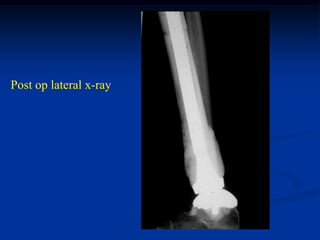

Post op lateral x-ray

AP x-ray showing